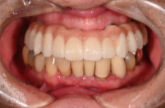

オールオン4の症例紹介②

Before

After

主訴

歯を入れたい

治療内容

上顎、下顎に対するインプラント治療を行った。

治療費

4,092,000円(税込)

治療期間

1か月

通院回数

3回

※治療回数は1回

想定されたリスク

※最終的な歯が入るまでは仮歯で過ごす必要がありました。

オールオン4は、少ないインプラント本数で多くの歯を補う治療法です。手術当日に仮歯を入れ、見た目と噛む機能をすぐに回復できます。